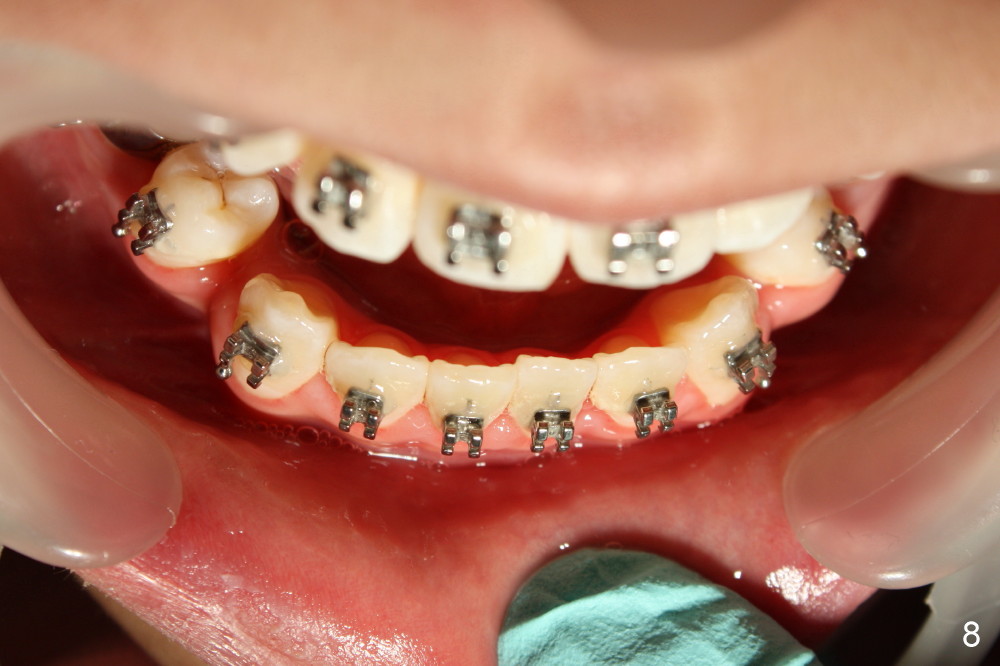

David, 16 years old, has severe crowding, midline deviation (Fig.1: dashed lines), and UL2 complete blockout (Fig.3: 2). Orthodontic treatment starts with extraction of four of the 1st bicuspids (Fig.2,3: .014 Niti).

Five weeks later, .018 ss wires are installed with open coil spring between UL 1 and 3 and power chain between UL 3 and 7 (Fig.4). Three months post-bracketing, space is being created for UL 2 (Fig.5). Four months post-bracketing, a lingual button is placed on UL2 with power chain x7 (Fig.6: sling shot); Pletcher's spring between UL 3 and 7 (^).